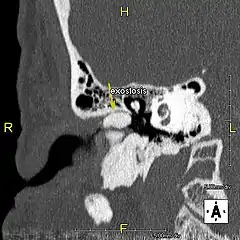

L'exostose du surfeur ou oreille de surfeur est une exostose, c'est-à-dire une croissance osseuse anormale, qui pousse vers l'intérieur du conduit auditif[1]. L'os entourant le conduit auditif réagit à l'agression thermique et mécanique de l'eau froide et de ses turbulences, par une nouvelle croissance osseuse qui a pour effet de resserrer le conduit auditif.

Du fait de la réduction du diamètre du conduit auditif, l'eau et le cérumen peuvent rester piégés entre la masse osseuse et le tympan et provoquer ainsi une infection comme une otite externe, particulièrement douloureuse.

Le traitement de l'exostose est chirurgical, de préférence avant une obstruction avancée. L’intervention, délicate et pouvant laisser des séquelles (perte d'audition, acouphènes…)[4] s'effectue sous anesthésie générale. L'abrasion de l'os s'effectue soit par le conduit auditif soit en faisant une incision derrière le pavillon de l'oreille. La préservation de la peau interne du conduit est déterminante pour la restauration d'une couverture cutanée optimale après l'opération.